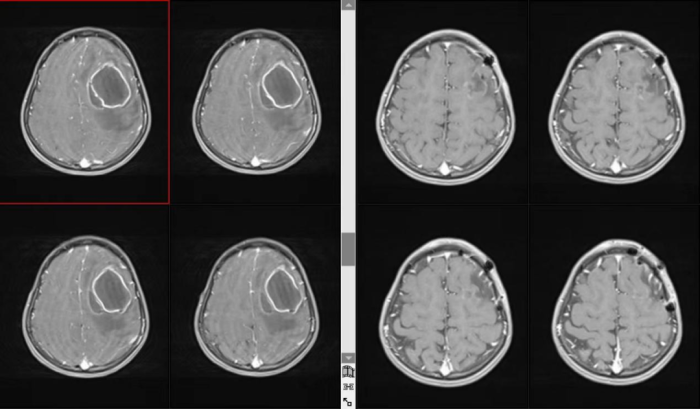

患儿因突发失语、右侧肢体偏瘫3天紧急入院,病情进展迅速,神经功能受损明显,家属十分焦急。科室接诊后高度重视,立即完善头颅磁共振增强等相关检查,迅速明确诊断为脑脓肿。由于病变位于重要神经功能区,压迫导致语言及运动功能障碍,病情凶险,若延误治疗极可能造成永久性神经功能损伤,甚至危及生命。

在科室主任李深誉主任医师带领下,医疗团队快速制定个体化、精细化的诊疗方案,为患儿实施了脓肿切除+引流手术。术中操作精准,最大限度保护正常脑组织,顺利完成颅内“拆弹”。术后早期联合康复医学科开展针对性肢体功能训练、言语康复训练及综合理疗,同时给予规范抗感染、营养神经、精细护理等全方位支持治疗。